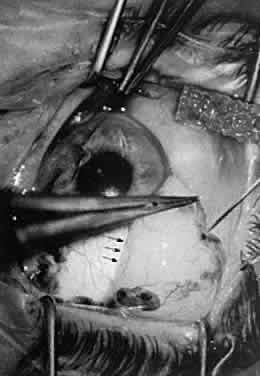

HEMOSTASIS Hemostasis commonly is achieved by applying heat to tissue, which causes

coagulation. Cauterization may range from interruption of blood flow

of vessels to blanching of tissue, gross charring of tissue, and in extreme

cases, tissue contraction (Fig. 30). The only way to monitor the application of heat is by anticipating the

power needs and visualizing the results. Care in this area is key to

controlling the delivery of heat to tissues. Excessive heat may cause

tissue contraction and wound deformation. Heat is generated in tissues

by monopolar or bipolar diathermy. Monopolar miniature diathermy probes

are used for intraocular coagulation. Bipolar diathermy is used to

generate heat in tissues either by grasping the tissue to be coagulated

or by applying indirect bipolar diathermy through a liquid film. With

either method of delivery, the bipolar diathermy unit requires that

the tissue to be coagulated remain between the probes of the diathermy

unit. Therefore, the forceps tips of the diathermy unit must be closely

approximated but not touching. As soon as the bleeding vessel coagulates, the

foot pedal should be released to limit tissue contraction. Changing

the voltage while keeping the space between the diathermy probes

constant controls the diathermy. In this way, increased voltage

results in increased energy delivery; however, in effect, keeping the

voltage constant and bringing the probes closer together increases the

energy delivered to the tissue. Delivery of excessive heat or energy

causes significant tissue shrinkage that may result in wound deformation.  Fig. 30. Hemostasis achieved through cauterization provides for interruption of

blood flow in vessels. The application of heat is monitored through visualizing

results. Excessive tissue shrinkage should be avoided. Coagulation

is visualized by the interruption of blood flow through the vessel. Fig. 30. Hemostasis achieved through cauterization provides for interruption of

blood flow in vessels. The application of heat is monitored through visualizing

results. Excessive tissue shrinkage should be avoided. Coagulation

is visualized by the interruption of blood flow through the vessel.